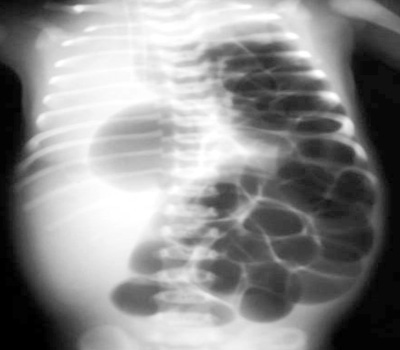

3: The most likely diagnosis is:

5: The most likely diagnosis is: